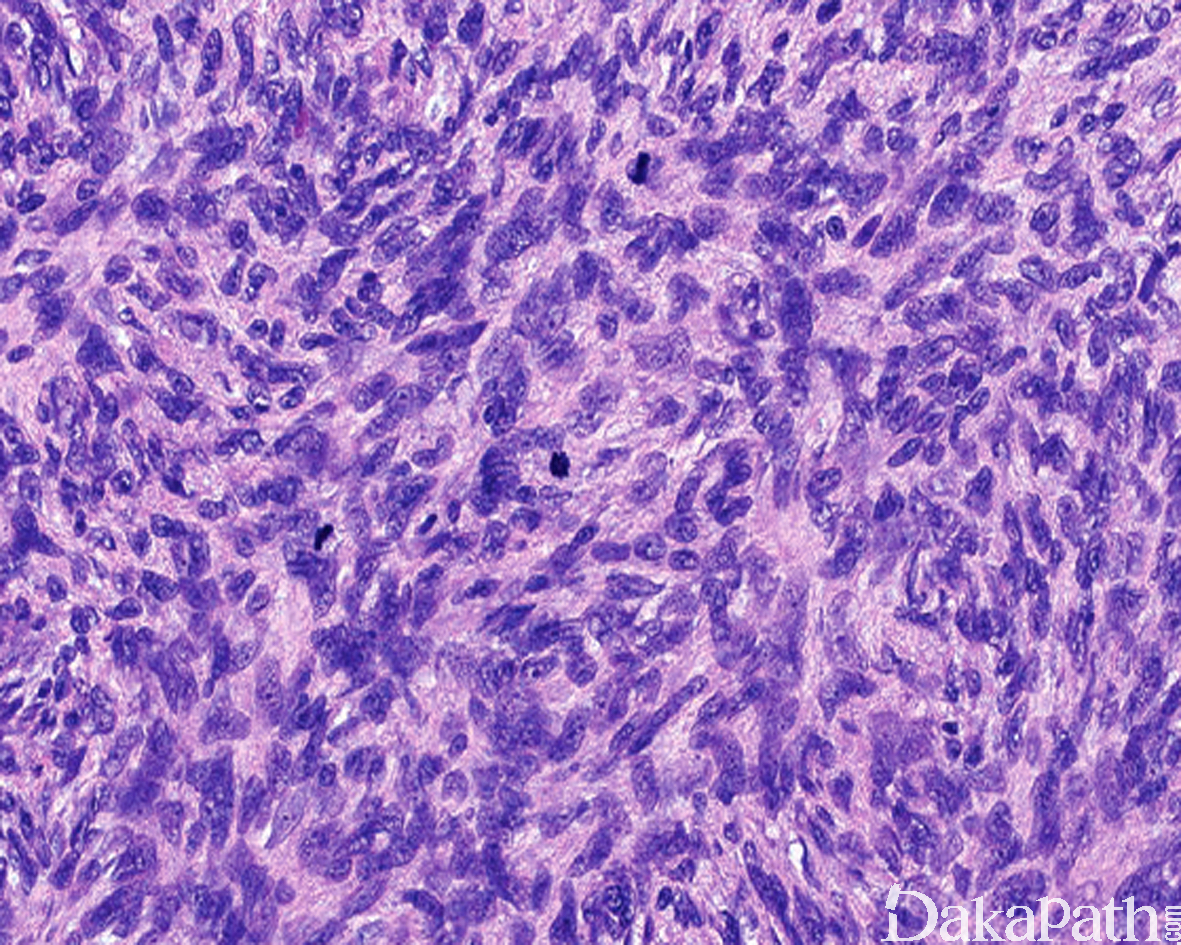

瘤细胞均匀较一致,呈两端细长的纤维母细胞样,呈一致的致密的席纹状排列,少数病例内可见局灶的血管外皮瘤样排列;

瘤细胞核异型性并不明显,核分裂像通常较低(0 ~ 10/10HPF);

约 10%的 DFSP 可见高级别转化,表现为瘤细胞密度高,呈长束状或鱼骨样排列,组织学上类似于成人型纤维肉瘤,又称为 DFSP 伴有纤维肉瘤样转化,纤维肉瘤样转化灶通常位于皮下,瘤细胞可见较大的异型性和明显增高的核分裂象,约 1%可见 DFSP 转化为明显的多形性瘤细胞特征,类似于多形性未分化肉瘤;